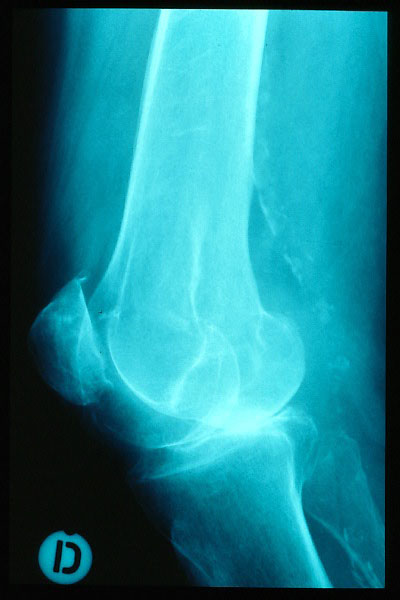

Fractura compleja de húmero.